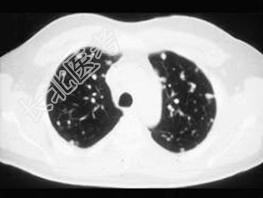

- 单项选择题女,72岁, 咳嗽,胸闷, 呼吸困难1月余,1年前行结肠癌根治术, CT检查如图,请选择最可能的诊断 ( )

B、肺转移瘤